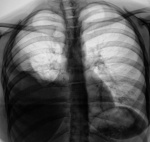

Пост 40. Осумкованный диафрагмально-пристеночный плевральный выпот с элементами организации. Что-то мне верхушка справа не нравится, как бы кавы не было.

Контроль после "флюшки".

Туберкулёз.

Пост 46: по обзорке диссеминированный поставил бы.